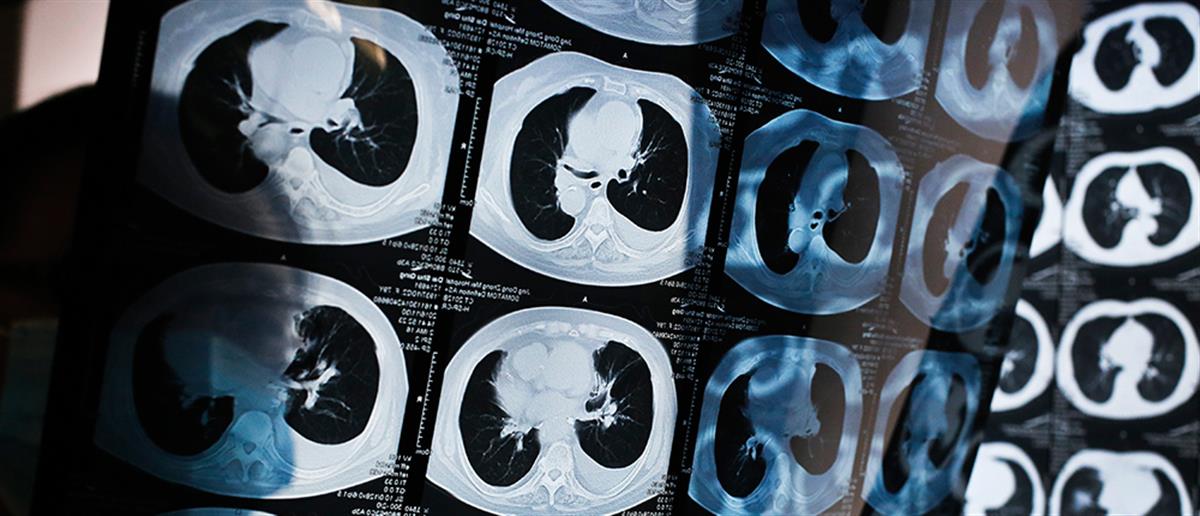

Το φάρμακο που αναπτύχθηκε και δίνει ελπίδα στη μείωση των θανάτων από καρκίνο του πνεύμονα.